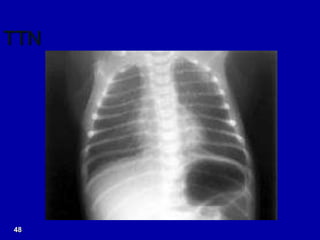

TTN

X-ray- TTNB

 X-Ray findings

– Prominent Perihilar streaking

– Hyperinflation

– Fluid in fissure

 Labs

– CBC within normal limits

– ABG/CBG showing mild to moderate

hypercapnia, hypoxemia with a respiratory

acidosis